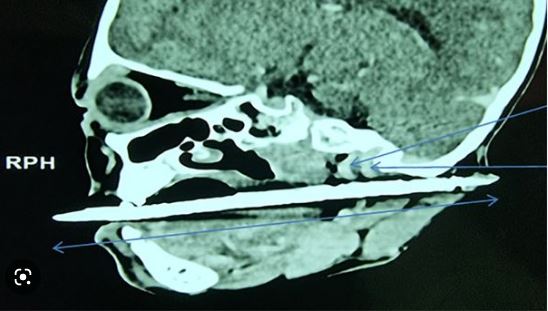

当地媒体报道,女童马上被送往附近医院,X光照清楚可见,发簪一端还在她嘴巴外,尖端从口腔穿过喉咙一路刺穿耳后,已经靠近颈内动脉和颈静脉。

所幸经过手术,发簪顺利从女童喉咙中取出。